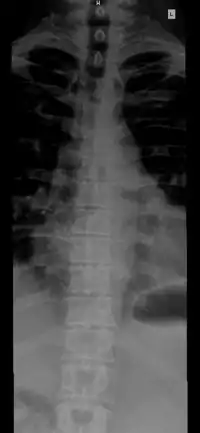

The vertebral column, also known as the backbone or spine, is part of the axial skeleton. The vertebral column is the defining characteristic of a vertebrate in which the notochord (a flexible rod of uniform composition) found in all chordates has been replaced by a segmented series of bone: vertebrae separated by intervertebral discs.[1] Individual vertebrae are named according to their region and position, and can be used as anatomical landmarks in order to guide procedures such as lumbar punctures. The vertebral column houses the spinal canal, a cavity that encloses and protects the spinal cord.

The number of vertebrae in a region can vary but overall the number remains the same. In a human vertebral column, there are normally 33 vertebrae.[3] The upper 24 pre-sacral vertebrae are articulating and separated from each other by intervertebral discs, and the lower nine are fused in adults, five in the sacrum and four in the coccyx, or tailbone. The articulating vertebrae are named according to their region of the spine. There are 7 cervical vertebrae, 12 thoracic vertebrae and 5 lumbar vertebrae. The number of those in the cervical region, however, is only rarely changed,[4] while that in the coccygeal region varies most.[5] One study of 908 human adults found 43 individuals with 23 pre-sacral vertebrae (4.7%), 826 individuals with 24 pre-sacral vertebrae (91%), and 39 with 25 pre-sacral vertebrae (4.3%).[6]

The vertebrae in the human vertebral column is divided into different regions, which correspond to the curves of the vertebral column. The articulating vertebrae are named according to their region of the spine. Vertebrae in these regions are essentially alike, with minor variation. These regions are called the cervical spine, thoracic spine, lumbar spine, sacrum, and coccyx. There are seven cervical vertebrae, twelve thoracic vertebrae, and five lumbar vertebrae.

Individual vertebrae are named according to their region and position. From top to bottom, the vertebrae are:

- Cervical spine: 7 vertebrae (C1–C7)

- Thoracic spine: 12 vertebrae (T1–T12)

- Lumbar spine: 5 vertebrae (L1–L5)

- Sacrum: 5 (fused) vertebrae (S1–S5)

- Coccyx: 4 (3–5) (fused) vertebrae (Tailbone)